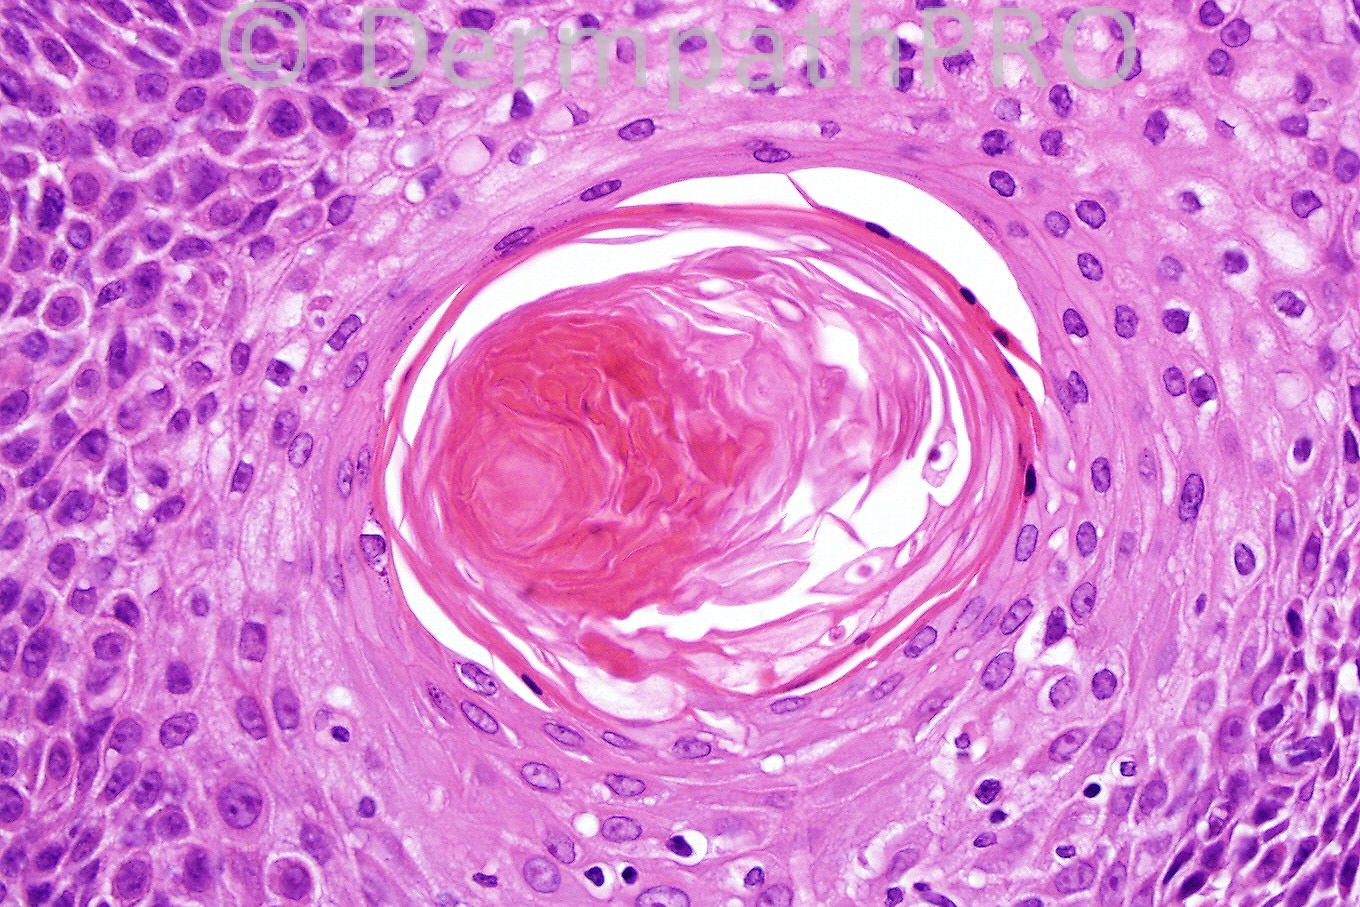

Female 76 years, rapidly growing tumor on face.